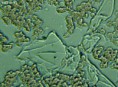

Mnohé štúdie dokazujú pozitívny efekt Bioquantu - jeho laserového žiarenia na postupnú elimináciu baktérií, vírusov či lariev parazitov migrujúcich v krvnom riečišti. Ide najmä o normalizáciu imunity, špecifickej i nešpecifickej. Navyše termodynamický efekt laseru pri ožarovaní krvi, ktorý síce náš organizmus nevníma a ľudské bunky neohrozuje, spôsobuje zvyšovanie termodynamickej teploty najmenších štruktúr - teda mikroorganizmov. Tieto následne ničí aktivovaná imunita a zvýšená baktericídna aktivita krvného séra. Sú zaznamenané pozitívne efekty pri vírusoch HIV/AIDS, vírusoch encefalitídy, pri borelióze, pri prevencii chrípky. O účinkoch na baktérie svedčí aj vysoká účinnosť pri výskytu akné baktérií. Prostredníctvom aktivácie porfírinov sa uvoľňujú voľné radikály a tým zabíjajú baktérie zvnútra..

Laserové ožarovanie krvi navodzuje i úpravu pomerov populácie T helperov a T supresorov smerom k normalizácii a úprave celkového počtu T lymfocytov a vyvoláva zmenu aktivity enzýmov imunokompetentných buniek. To je dôležité pre celom rade ďalších ochorení.